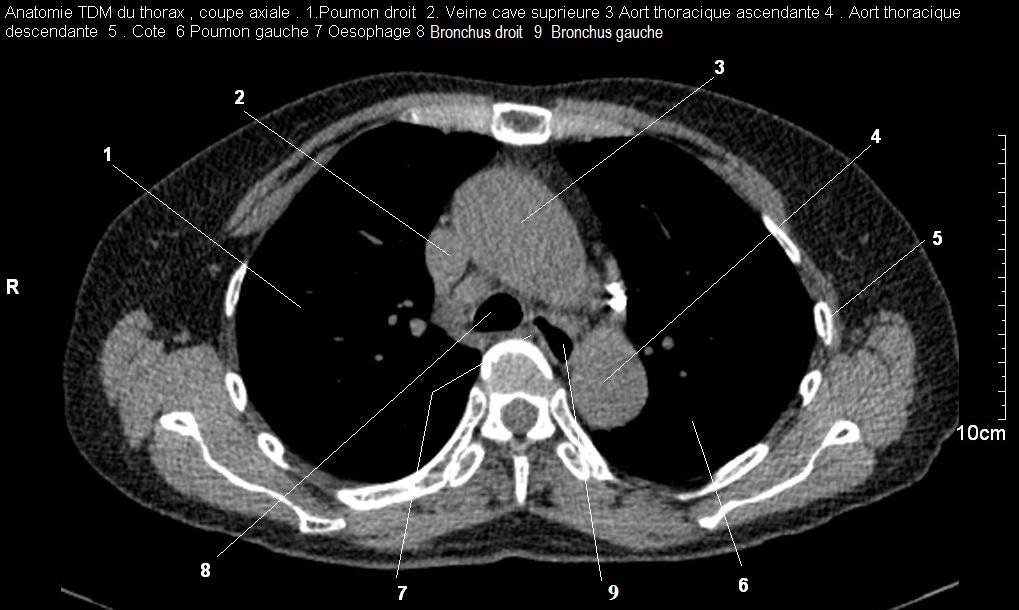

Image radiologique TDM normal , coupe

axiale , fenetre mediastinale du bronchous droit et

gauche . Le bronchus droit est en aspect

arrondie hypodense très nette , bronchous gauche

ovalaire , lisse , nette très hypodensite de vide en

avant , pres de os vertebral TH3-4 . (

click pour entrer ) |